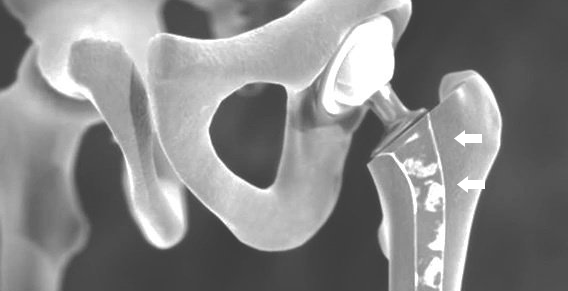

EN LA ARTICULACIÓN DE LA CADERA, EN PARTICULAR INFECCIÓN del material de la prótesis, postinterminación precoz del eje o fractura del hueso que afecta a los implantes, se temen como complicaciones.

La OFT se puede volver a operar con un implante primario de cadera al reemplazar la prótesis. En ocasiones también son necesarios implantes de revisión especiales.